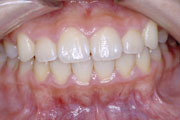

症例3:開咬(オープンバイト)